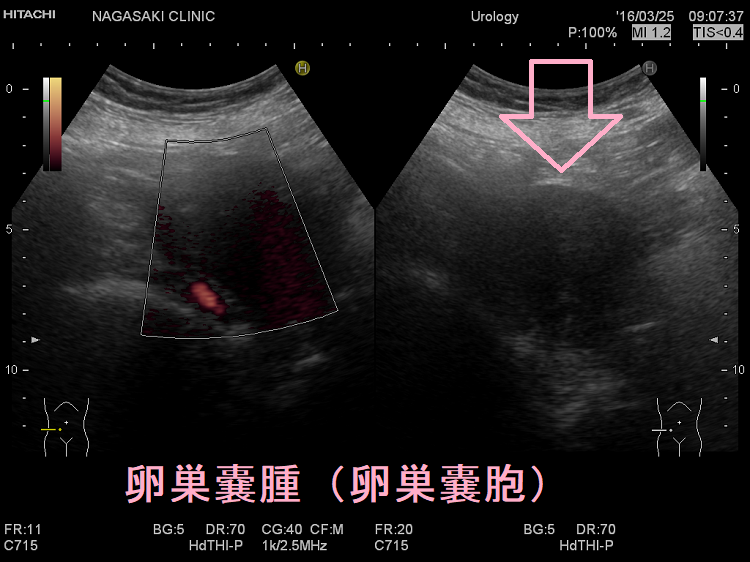

長年に渡る重度の甲状腺機能低下症により、粘液多糖類(ヒアルロン酸、コンドロイチン硫酸塩)沈着と卵胞発育異常が生じ、卵巣容積増加・卵巣嚢胞(卵巣嚢腫)形成促進。卵巣茎捻転の危険。甲状腺ホルモン補充療法により甲状腺機能正常化すると、遅れて卵巣容積・卵巣嚢胞減少。チョコレートのう胞(卵巣子宮内膜症)は生理周期に合わせて子宮内膜剥離出血し、生理痛・不妊症・破裂して急性腹症。甲状腺乳頭癌術後のDWIBSで偶然発見される。過剰なエストロゲン刺激に関連する甲状腺疾患などが危険因子となり、約1%が子宮内膜症関連卵巣癌(EAOC)に悪性転換。

長年に渡る重度の甲状腺機能低下症により、卵巣容積は増加し、卵巣嚢胞形成が促進されます。

甲状腺ホルモン補充療法により甲状腺機能が正常化すると、遅れて卵巣容積・卵巣嚢胞の減少が起こります。(Ann Saudi Med. 2011 Mar-Apr;31(2):145-51.)

プロラクチン産生下垂体腺腫(高プロラクチン血性下垂体腺腫、プロラクチノーマ)でも、未熟な卵胞による卵巣嚢腫が多発[多嚢胞性卵巣(PCO)、多嚢胞性卵巣症候群(PCOS)とは異なる]します。頻繁に卵巣嚢腫が再発する場合、プロラクチン産生下垂体腺腫(高プロラクチン血性下垂体腺腫、プロラクチノーマ)を疑わねばなりません。

プロラクチン産生下垂体腺腫(高プロラクチン血性下垂体腺腫、プロラクチノーマ)でなくても、下垂体過形成に至る重度の原発性甲状腺機能低下症では、TSH(甲状腺刺激ホルモン)のゴナドトロピン様作用で卵巣嚢腫を来します[Cureus. 2021 Feb 26;13(2):e13573.]。(下垂体過形成の症状)